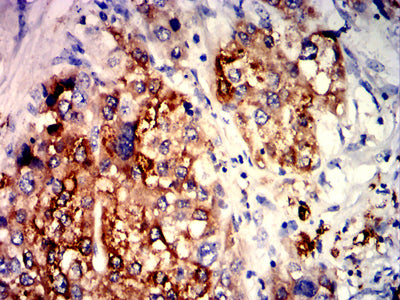

![C5AR2 Mouse mAb[63180]](https://img1.dxycdn.com/p/s14/2025/0922/015/2536973524282699691.jpg)

Immunohistochemical analysis of paraffin-embedded human liver cancer tissues using C5AR2 mouse mAb with DAB staining.